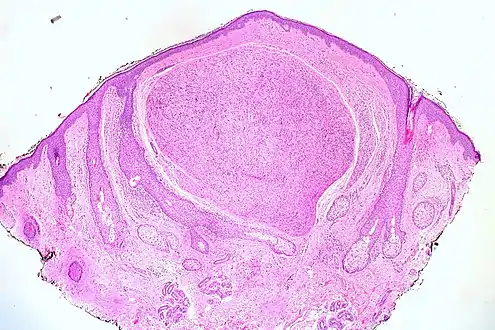

| Micrograph of a palisaded encapsulated neuroma | |

Skin tumors(palisaded encapsulated neuroma)